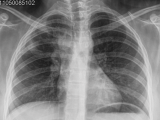

Se le realizó en la primera consulta una radiografía de tórax, que fue interpretada como normal. Los meses posteriores presentó expectoración sanguinolenta, dolor intenso en región interescapular y paravertebral derecha.

En una nueva radiografía de tórax (Fig.1) se apreció una lesión infiltrativa alveolar en campo superior del pulmón derecho, leve ensanchamiento mediastinal homolateral, sin ocupación pleural, y se interpreta el cuadro como una neumonía aguda de la comunidad por el Servicio de Neumonología, y se indicó tratamiento antibiótico con leve mejoría de su sintomatología. Un mes posterior, consultó nuevamente con dolor cervical y braquial de 3-4 días de evolución, intenso, asociado a un cuadro de lipotimia. En el examen físico presentó contractura cervical, pulso radial +, miembro superior derecho edematizado, caliente, con cianosis y circulación venosa prominente.